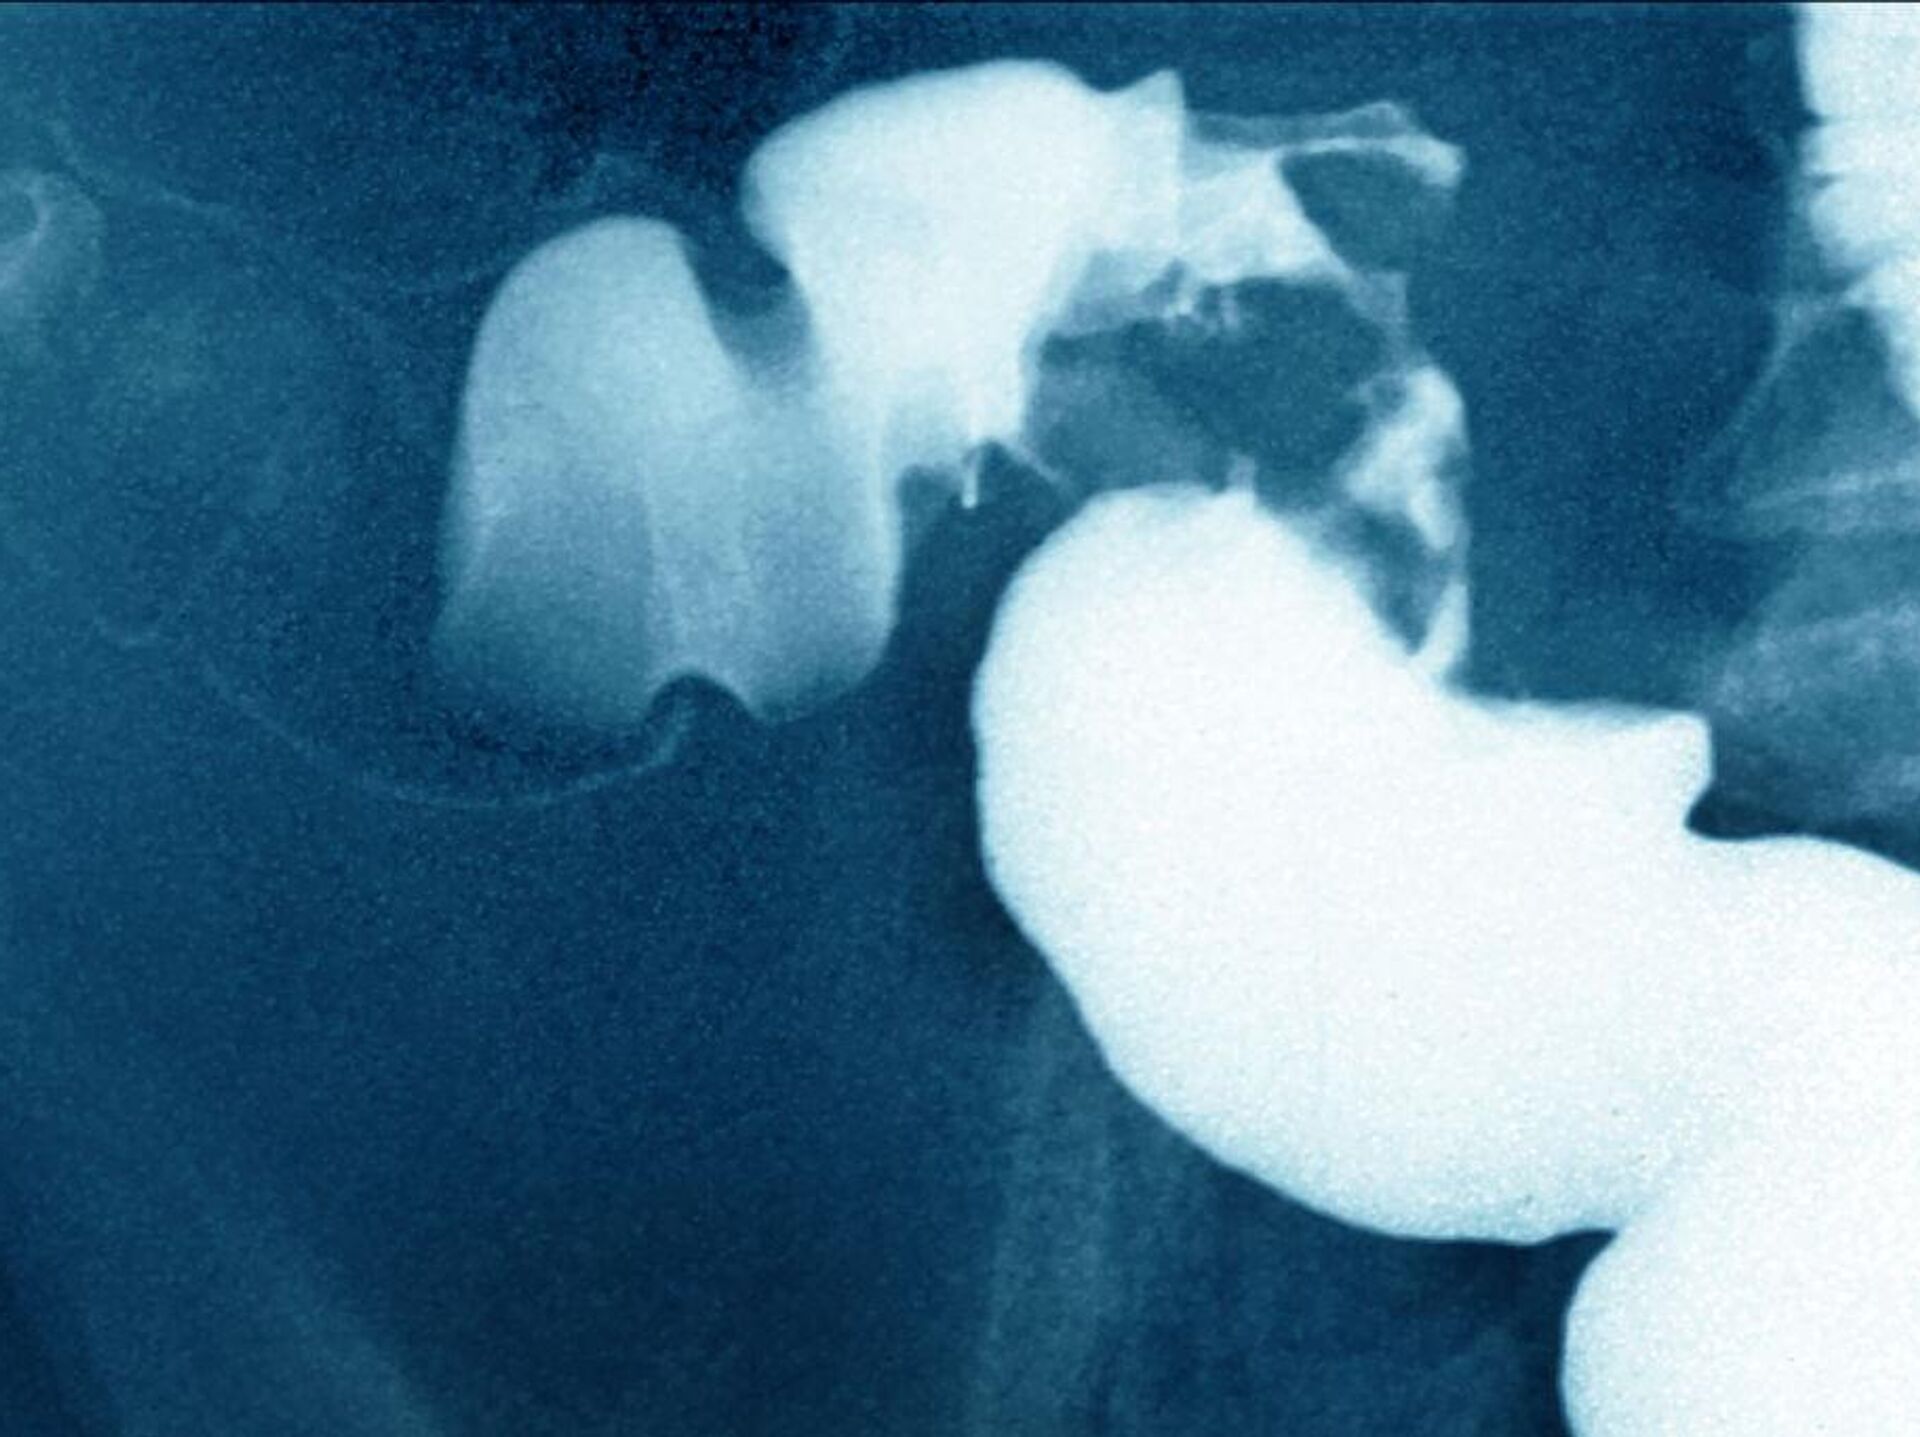

دراسة جديدة تكشف علاقة الزبادي بسرطان القولون

© Getty Images / BSIP / Contributorسرطان القولون

سرطان القولون - سبوتنيك عربي, 1920, 22.02.2025

توصلت دراسة حديثة إلى أن تناول علبتين من الزبادي أسبوعيًا قد يحمي الأمعاء من بعض أنواع السرطان وخاصة سرطان القولون.

ذكر ذلك موقع "ساينس أليرت"، اليوم السبت، مشيرا إلى أن الدراسة تم إجراؤها على فترة طويلة، مشيرة إلى أنها أوضحت أمورا كانت محل شكوك بالنسبة لعلاقة الزبادي بتقليل فرص الإصابة بهذا المرض.

فبينما كانت الدراسة التي يتم إجراؤها بصورة عامة لا تظهر علاقة بين استهلاك الزبادي وسرطان القولون والمستقيم عمومًا، فإن إجراء الأبحاث بصورة أكثر تفصيلا سمح بالتوصل لنتائج جديدة.

وتقول الدراسة إن الأشخاص الذين تناولوا علبتين أو أكثر من الزبادي أسبوعيا، كانوا أقل عرضة للإصابة بأورام إيجابية بنسبة 20 في المئة، مقارنة بمن يستهلكون أقل من علبة واحدة شهريًا.

وكانت هذه العلاقة أقوى بالنسبة للأورام في الجزء العلوي من الأمعاء، مما يشير إلى دور محتمل للبكتيريا في الحد من تطور هذه الأورام.

ويرى الباحثون أن هذه البكتيريا قد تمتلك خصائص مضادة للأكسدة والالتهابات وتعزز المناعة، مما قد يساعد في زيادة قدرة الجسم على مقاومة المرض.

وتعزز هذه الدراسة فرضية أن استهلاك الزبادي قد يكون عاملًا وقائيًا ضد سرطان القولون المرتبط بضعف الحاجز المعوي، لكنها تستدعي المزيد من الأبحاث لفهم الآليات الخاصة بهذا الأمر.